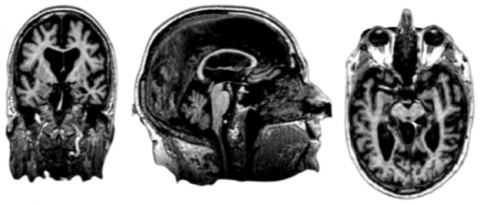

T1 MRI images were pre-processed by Hua et al. [40] and prepared for TBM analysis. In brief, all images were resampled to 1mm voxel sizes in x, y, and z dimensions, then non-linearly aligned to a group-average template created with 40 randomly selected control subjects, and individual Jacobian maps were estimated from the warp-fields. Deformation fields calculated for deformation-based morphometry and TBM are shown in Figure 2 [39].

The DBM field calculates the large-scale difference between the subject image and template image, whereas the TBM field calculates local differences. TBM is a mapping method applied to MRI images to visualize brain tissue loss and enlargement. Figure 3 shows MRI image of an AD subject in the ADNI database.

Figure 2. Differences between a) DBM and b) TBM [39]

Figure 3. Original MRI scan image of a single subject: a) Coronal MRI slice, b) Sagittal MRI slice and c) Axial MRI slice

Figure 4. TBM image of the subject: a) Coronal slice; b) Sagittal slice; c) Axial slice